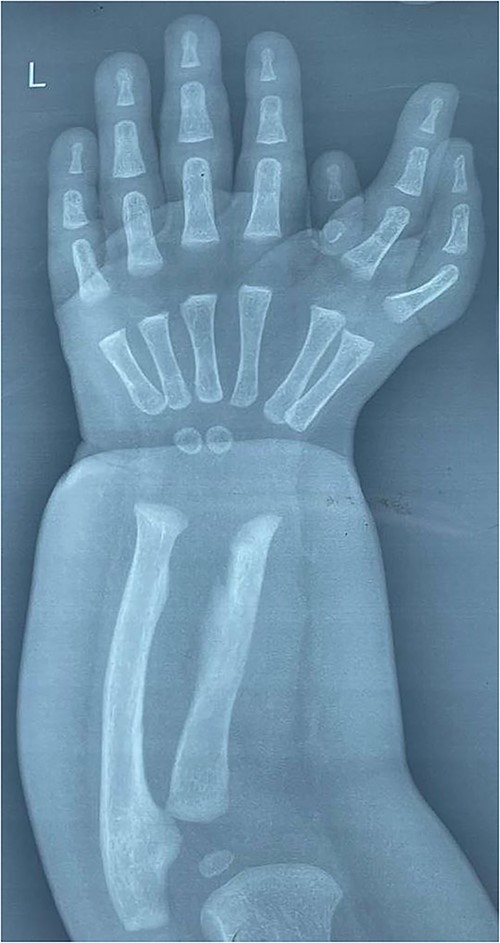

Follow-up after 5 months reveals normal function hand (Fig. 4).

Photographs of the hand 5 months after pollicisation showing normal functiong hand.